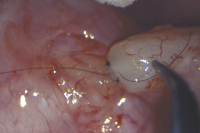

Refertilisierung und ICSI bei obstruktiver Azoospermie

Journal für Reproduktionsmedizin und Endokrinologie - Journal of Reproductive Medicine and Endocrinology 2010; 7 (5): 408-412 Volltext (PDF) Summary Praxisrelevanz Abbildungen